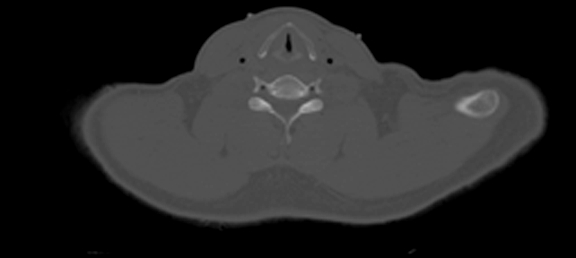

Horizontal CT Section at this level